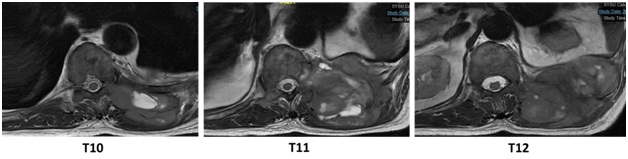

第一例手术患者,是一位69岁男性,诊断为左侧第11肋骨骨巨细胞瘤伴恶变,病灶侵及左侧第10、11、12肋骨,并累及胸10椎弓根及附件(WBB分区:2-3区,A-B层)、胸11部分椎体、椎弓根及附件(WBB分区:2-5区,A-C层)、胸12横突(WBB分区:2-3区,A-B层)。

核磁共振(T2加权)显示病例一胸椎的病灶范围